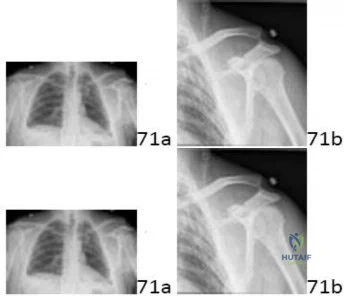

A 22-year-old overhead throwing athlete complains of deep shoulder pain during the late cocking phase of throwing. MR arthrography reveals a Type II Superior Labrum Anterior to Posterior (SLAP) tear. Which of the following best describes the specific anatomical pathology of a Type II SLAP lesion?